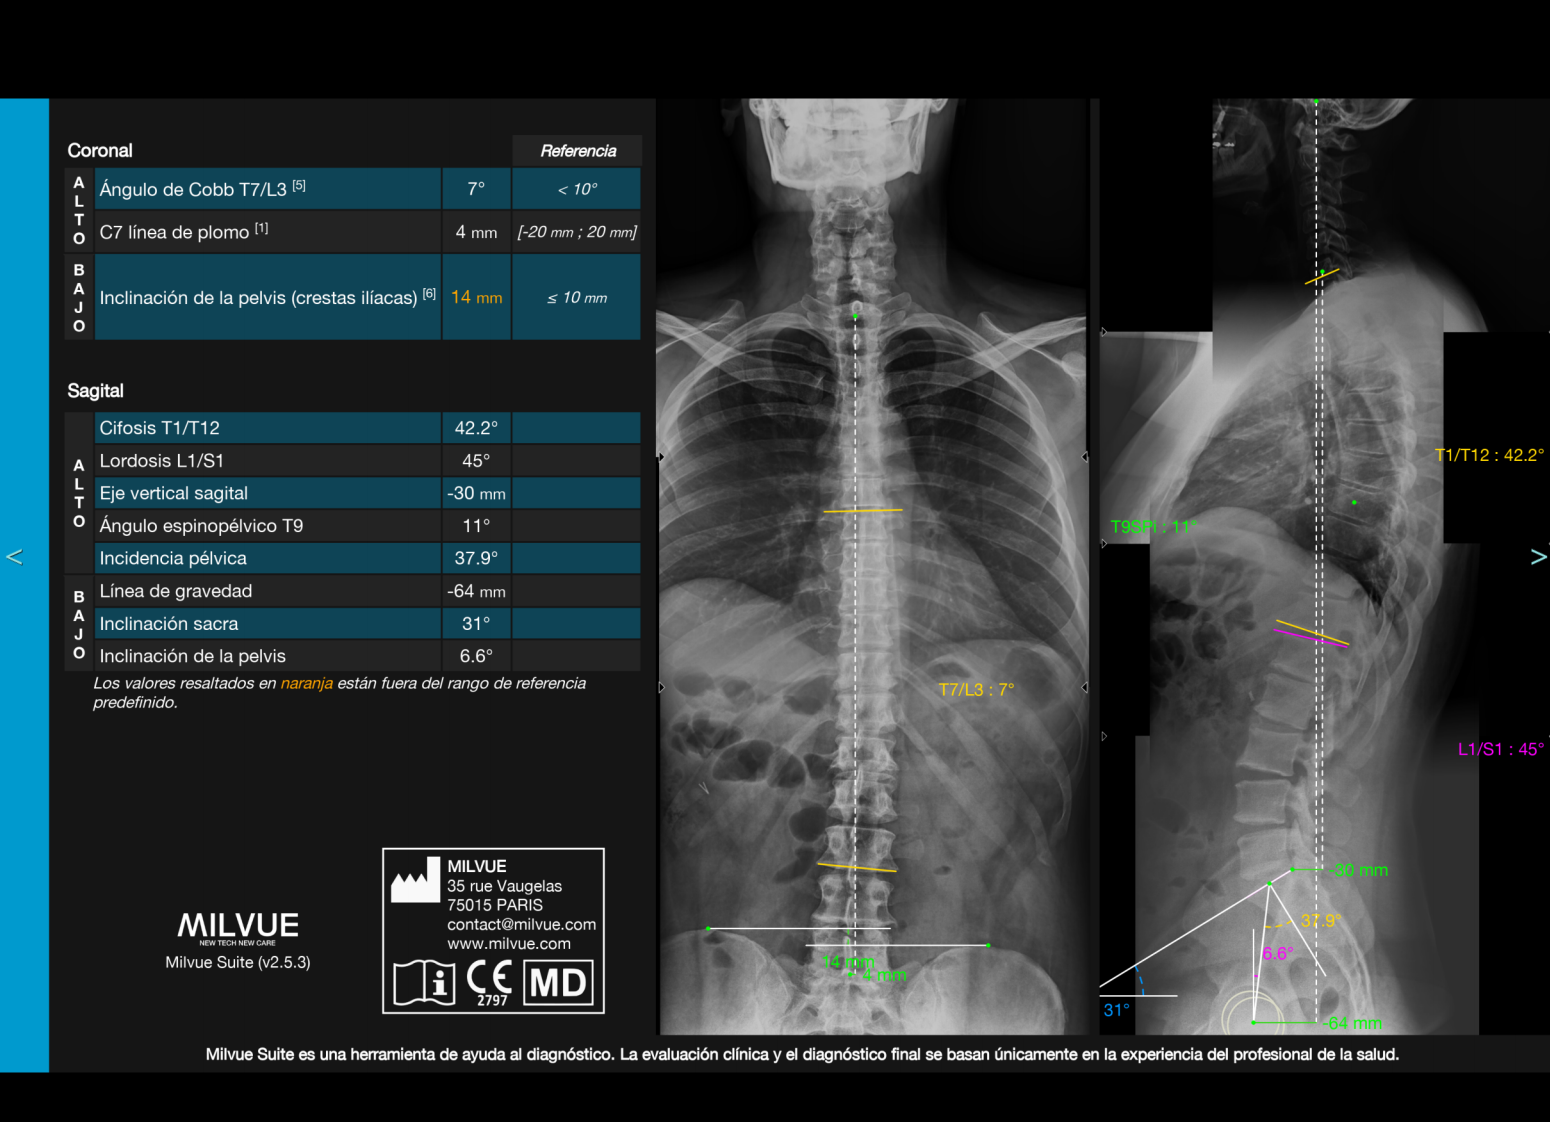

IA para Rayos X – Milvue

Milvue es una solución líder en inteligencia artificial aplicada a Rayos X, especialmente en el área musculoesquelética, con impacto clínico demostrado en servicios de urgencias.

#1 en detección automática de fracturas.

Detección de múltiples patologías en una sola imagen.

Reducción del tiempo de espera hasta en 1 hora.

Incremento del 20–30% en eficiencia diagnóstica.